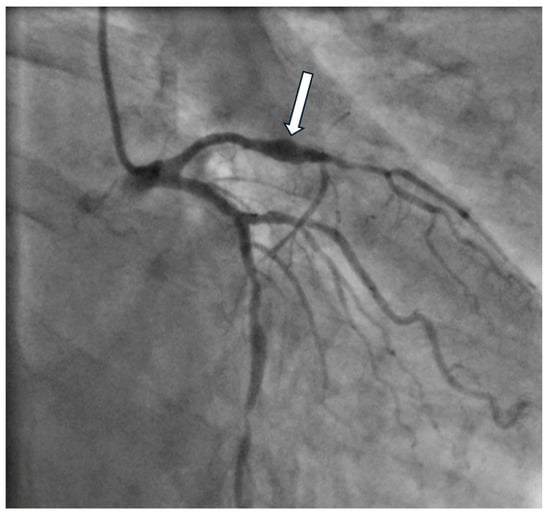

Invasive assessment of CAAE is based on coronary angiography (Figure 2). Nevertheless, this technique has limitations, as the actual size of the aneurysm may be underestimated in the presence of a thrombus. Furthermore, the turbulent flow in the dilated coronary segment can impair optimal imaging during coronary angiography []. Suboptimal imaging of the aneurysm hinders a thorough evaluation, including the presence of a thrombus. In such cases, intravascular ultrasound (IVUS) can be conclusive. Intracoronary imaging is a helpful tool for assessment of the accurate size of CAA, distinguishing between true aneurysms, pseudoaneurysms, and segments imitating aneurysms due to plaque rupture or adjacent stenosis, as it provides more precise visualization of vessel wall structures (Figure 3 and Figure 4). IVUS also allows proper stent sizing if percutaneous coronary intervention (PCI) is necessary.

Figure 2. Coronary angiograms showing (A) saccular aneurysm of the right coronary artery (arrow), (B) saccular aneurysm of the mid-segment of the left anterior descending artery (arrow), (C) fusiform aneurysm of the left anterior descending artery (arrow), (D) saccular aneurysm of the left main coronary artery (arrow), (E) coronary artery ectasia of the right coronary artery, and (F) coronary artery ectasia of the left circumflex artery.

Figure 3. Coronary angiography of the saccular aneurysm (arrow) in the mid-segment of the left anterior descending artery.